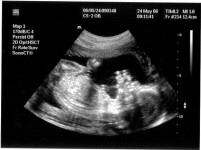

Regular monitoring of blood pressure occurs during any pregnancy. Blood pressure elevation can occur in women who were previously known to have hypertension, or may develop during the course of the pregnancy, so called “gestational hypertension”.

Hypertensive complications of pregnancy can be major cause of risk to mother and baby. The major complications to avert are the conditions of “pre-eclampsia” and “eclampsia” (see later).

These are worrying conditions, and extra care is required to avoid harm to mother and baby. Pre-eclampsia is defined as the development of significant hypertension beyond 20 weeks with protein in the urine. The detection of significant protein in the urine (proteinuria) may signify potential risk. Eclampsia is a more serious condition heralded by the onset of convulsive fit and is managed very intensively in a specialist centre.

Women at higher risk of developing pre-eclampsia include: a history of blood pressure in previous pregnancies, auto-immune conditions, diabetes, or long term hypertension. In such cases increased supervision is required from the outset, and daily aspirin 75 mg from 12 weeks onwards. Patients diagnosed with pre-eclampsia are admitted to hospital in the first instance. With blood pressures greater than 150/100 mmHg, medication will be required, and pressure needs to be maintained below that. Regular monitoring of mother and baby is undertaken with blood and urine tests and fetal monitoring. Discussions would follow as to potentially delivering the baby if there is perceived risk.